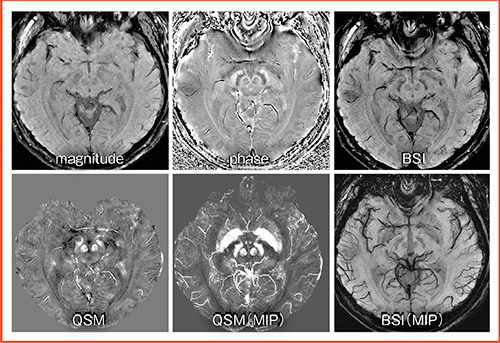

図4は,L1-Norm regularizationを用いた3T MRIのQSM画像である8)。位相画像やBSI(blood sensitive imaging:SWIに相当)に含まれていたアーチファクトが,QSMでは大幅に低減できている。

図4 L1-Norm regularizationを用いた3T QSM画像

文献8)より引用転載